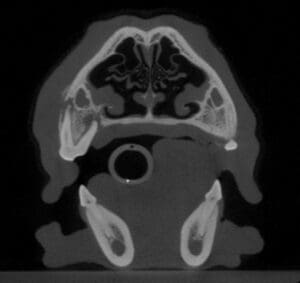

Here are some example cases of tooth infections. In the case shown below, the dog’s left upper fourth premolar was fractured but the pulp was not directly exposed. One day the dog developed a swelling under her left eye. A cone beam CT showed that the tooth had died and the infection around the roots caused bone loss (called a periapical lucency) that spread into the nose. Fortunately extracting the tooth went smoothly and the swelling on the face resolved.